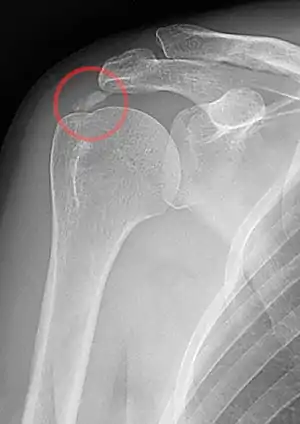

A plain X ray of the shoulder showing calcific tendinitis

Calcific tendinitis is a common condition where deposits of calcium phosphate form in a tendon, sometimes causing pain at the affected site. Deposits can occur in several places in the body, but are by far most common in the rotator cuff of the shoulder. Around 80% of those with deposits experience symptoms, typically chronic pain during certain shoulder movements, or sharp acute pain that worsens at night. Calcific tendinitis is typically diagnosed by physical exam and X-ray imaging. The disease often resolves completely on its own, but is typically treated with non-steroidal anti-inflammatory drugs to relieve pain, rest and physical therapy to promote healing, and in some cases various procedures to breakdown and/or remove the calcium deposits.